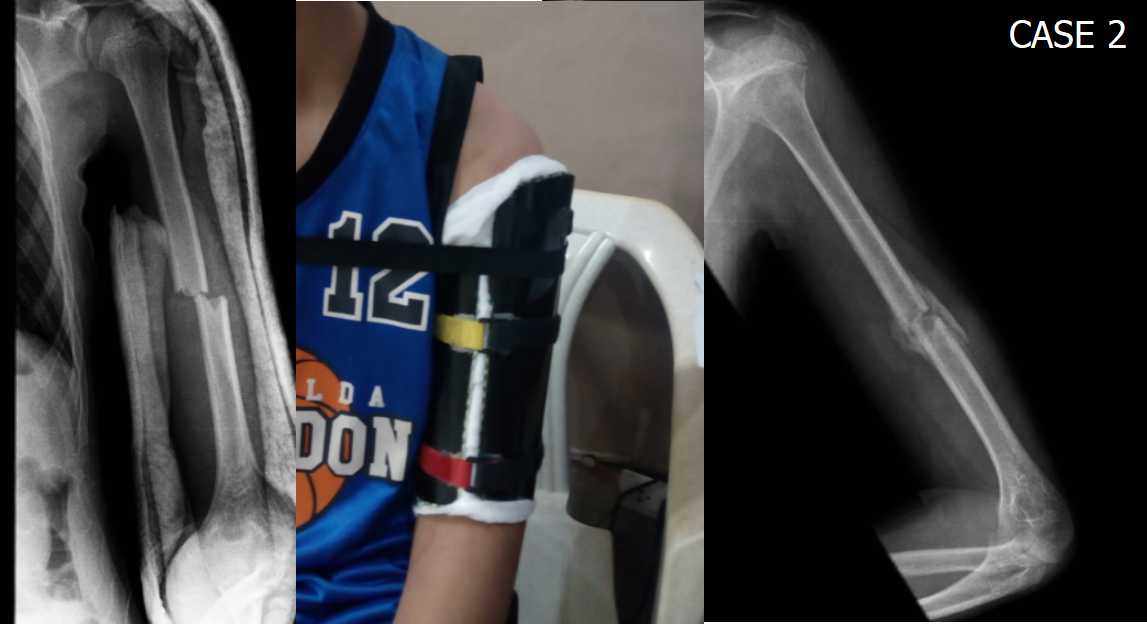

From orthopodsworkbench.blogspot.com

. MAKING HUMERAL FRACTURE BRACES USING PVC PIPES Pvc Pipe Braces the oatey pipe support bracket with insulator pipe clamps is designed to support copper, cpvc and pex piping. get free shipping on qualified pvc brackets products or buy online pick up in store today in the building materials department. shop for pipe support brackets at ferguson. our pipe support brackets include stub outs for bracing pipe. Pvc Pipe Braces.

. MAKING HUMERAL FRACTURE BRACES USING PVC PIPES Pvc Pipe Braces Find adjustable bracket pipe support & clamps at lowe's today. get free shipping on qualified pvc brackets products or buy online pick up in store today in the building materials department. Shop pipe support & clamps and a variety of plumbing products online at. the oatey pipe support bracket with insulator pipe clamps is designed to support copper,. Pvc Pipe Braces.

. MAKING HUMERAL FRACTURE BRACES USING PVC PIPES Pvc Pipe Braces Shop pipe support & clamps and a variety of plumbing products online at. Ferguson is the #1 us plumbing supply company and a top distributor of hvac. the oatey pipe support bracket with insulator pipe clamps is designed to support copper, cpvc and pex piping. get free shipping on qualified pvc brackets products or buy online pick up. Pvc Pipe Braces.